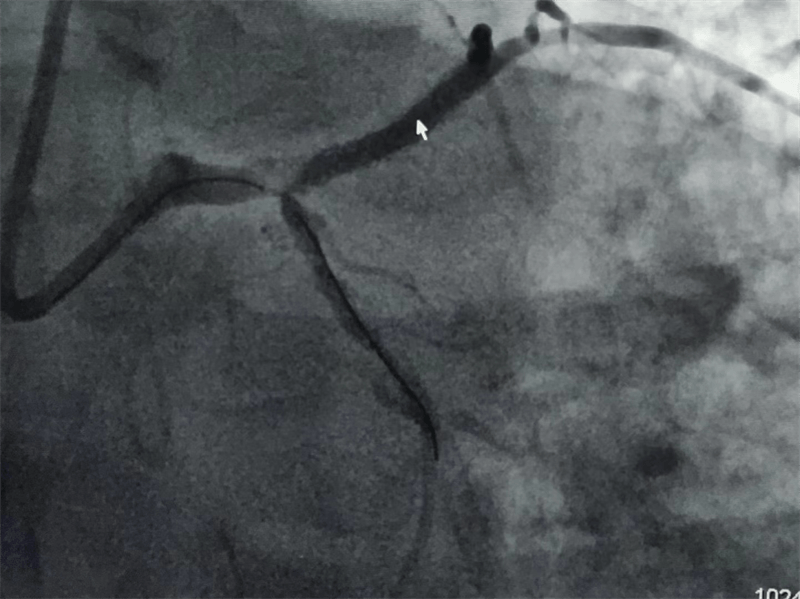

冠脈造影結果提示:左主干末端及前降支開口處99%狹窄,回旋支開口處80-90%狹窄,中段支架內100%閉塞。看到造影結果時,在場醫護人員無不驚出一身冷汗:左主干病變“細”如發絲——生死一線牽!患者拒絕搭橋手術,所以選擇介入處理該病變。

挽救患者生命,挽救一個家庭的希望!當導絲通過病變區域時,大家的心都緊張了起來,經過精細、快速的操作,手術順利完成,原來像頭發絲一樣粗細的“血路”,終于恢復了正常!

我們結合患者病變特點,對回旋支支架內閉塞病變處藥物球囊治療,左主干病變植入1枚支架,術后,造影顯示左主干病變處支架植入狀態良好,血管內超聲顯示支架貼壁良好,患者血壓、心率穩定,癥狀完全緩解,并安全返回重癥監護室進一步治療,術后張大伯無明顯不適,生命體征穩定,病情明顯好轉。